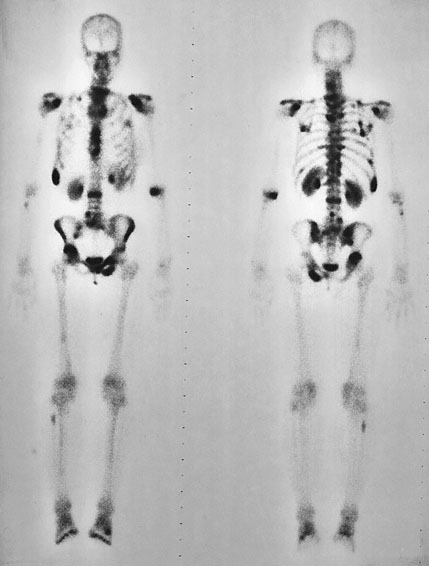

A 58-year-old man comes to the office because of a 4-month history of increasingly severe back and rib pain. He has hypertension and hypercholesterolemia. Current medications are atenolol and atorvastatin. He does not smoke cigarettes and does not drink alcoholic beverages. Vital signs are temperature 37.7°C (99.9°F), pulse 75/min, respirations 16/min, and blood pressure 132/86 mm Hg. Pressure applied over the lower rib cage and the hips bilaterally elicits pain. The result of a bone scan is shown. Pathologic examination of this patient’s primary tumor is most likely to show which of the following?